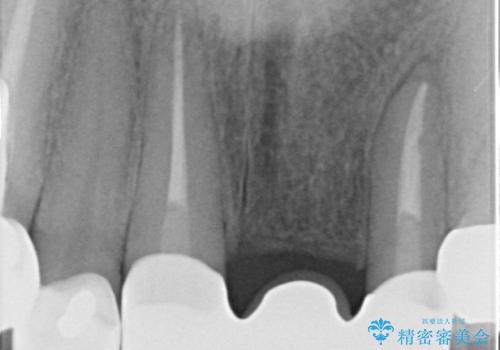

歯肉縁下カリエスも認められるため、挺出を行いセラミックブリッジを審美的に新製します。

挺出について

虫歯が深くなった場合、挺出や歯周外科を行い歯周組織の状態を改善することでより安定した状態で予知性の高いセラミックブリッジを製作することが可能となります。